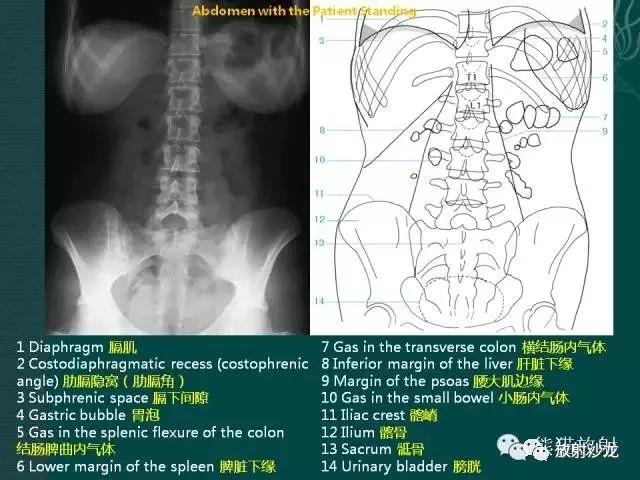

腹部平片解剖

腹部平片正常表现

腹部平片注意事项

消化道穿孔 = 膈下月牙形游离气体。

急性肠梗阻 = 多个阶梯状液平。

泌尿系阳性结石 = 泌尿系路径上有高密度阴影(亮点)。

注意:

①诊断消化道穿孔时,不要将胃泡影、靠近膈肌下的阶梯状液平等误认为膈下游离气体。阅片时首先找到膈肌,其下的黑色月牙形阴影即为膈下游离气体,此为消化道穿孔的特征性X线表现。膈下游离气体常以右侧明显,左侧被胃掩盖,常不明显。

②正常人也可有少量液平面,因此不能发现液平,就诊断为急性肠梗阻,应结合病史。

③诊断泌尿系阳性结石时,应沿“肾脏→输尿管→膀胱”的径路,在脊柱两旁观察有无高密度亮点。